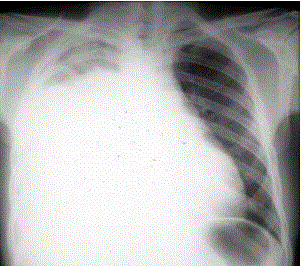

患者男,34岁。进行性胸闷、气促1个月余,伴有干咳、右胸隐痛以及消瘦,无咯血、发热、盗汗、潮热等。(提示 胸部X线检查如图所示)考虑患者目前出...

问题 患者男,34岁。进行性胸闷、气促1个月余,伴有干咳、右胸隐痛以及消瘦,无咯血、发热、盗汗、潮热等。 (提示 胸部X线检查如图所示) 考虑患者目前出现的情况是(提示 为解决患者胸闷、气促症状,给予胸腔插管引流胸腔积液,一次性放出淡黄色胸腔积液约1 800 ml。患者引流后自觉气促症状减轻,但半小时后渐觉胸闷、呼吸困难再次加重,剧咳伴咳大量泡沫样痰。查体:端坐呼吸,口唇发绀,双肺满布湿性啰音,心率130次/min,律齐。)

选项 A.急性肺血栓栓塞症 B.急性呼吸窘迫综合征 C.肺复张后肺水肿 D.胸膜反应 E.医源性气胸 F.急性左心衰竭 G.胸腔内出血

答案 C